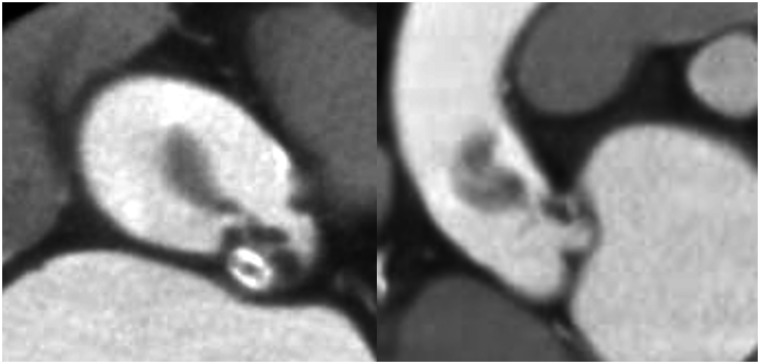

Figure 4.

Intravascular ultrasound showing no dissection of the coronary artery or proximal ascending aorta, and showing that the thrombus extended from the ascending aorta to the proximal left anterior descending artery. LAD, left anterior descending coronary artery; LMCA, left main coronary artery.